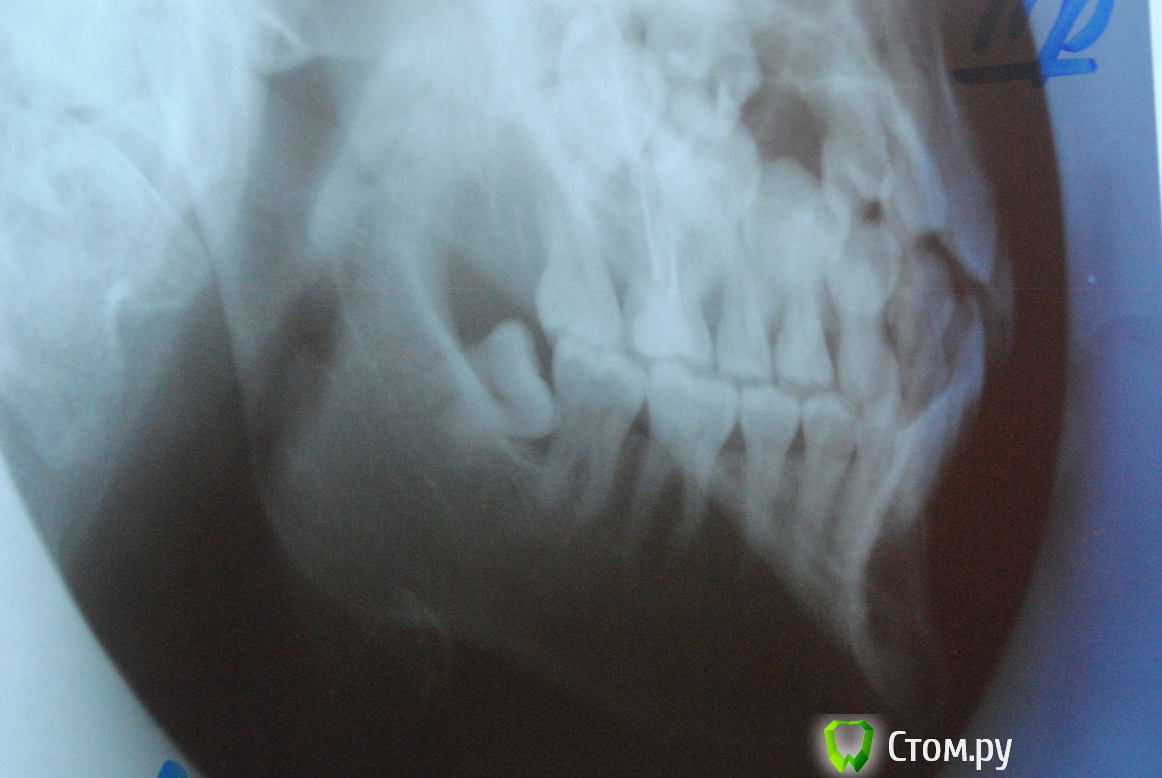

Irson Опубликовано 10 ноября, 2014 Поделиться Опубликовано 10 ноября, 2014 Уважаемые доктора, здравствуйте! Прошу вашего совета. Неделю назад у меня появилась боль и припухлость десны в области ретинированной 8-ки снизу, образовался гнойник. Боль умеренная, в области нарыва, немного при глотании. Поласкала содой, гнойник прорвался, но через неделю образовался снова. Сделала снимок. При осмотре мне назначили антибиотикотерапию цифран 3 раза в день по 500 мг - 3 дня и найз по 1 т. 3 раза в день - 3 дня. Промыли хлоргексидином и положили лекарство(названия не знаю). Сказали, что зуб нужно удалять. Скажите пожалуйста, как срочно нужно удалить зуб? Могу ли я подождать три недели(так как у меня очень важная поездка) или это опасно и могут быть осложнения? Посоветуйте пожалуйста место в Москве, где лучше всего удаляют такие зубы? Очень боюсь. Заранее спасибо за ответ. Снимки: панорамный 2 года назад и прицельный сегодня. Ссылка на комментарий

SDC Опубликовано 10 ноября, 2014 Поделиться Опубликовано 10 ноября, 2014 (изменено) Если 3 недели до поездки, то сейчас лучшее время для удаления.Удаляя зуб за 2-3 недели до отъезда, Вы имеет в запасе время для реабилитации и страхуетесь от осложнений в поездке.Справедливости ради, судя по представленному снимку, ничего серьезного не произойдет и через 2, и через 3, и через 6 недель. )) Для хорошей очистки десневого кармана в обл. 48 зуба и снижения риска обострения до минимума нужен ирригатор.По поводу удаления не беспокойтесь, зуб из разряда обычных, хирург с минимальным опытом способен быстро его удалить. Изменено 10 ноября, 2014 пользователем SDC 1 Ссылка на комментарий